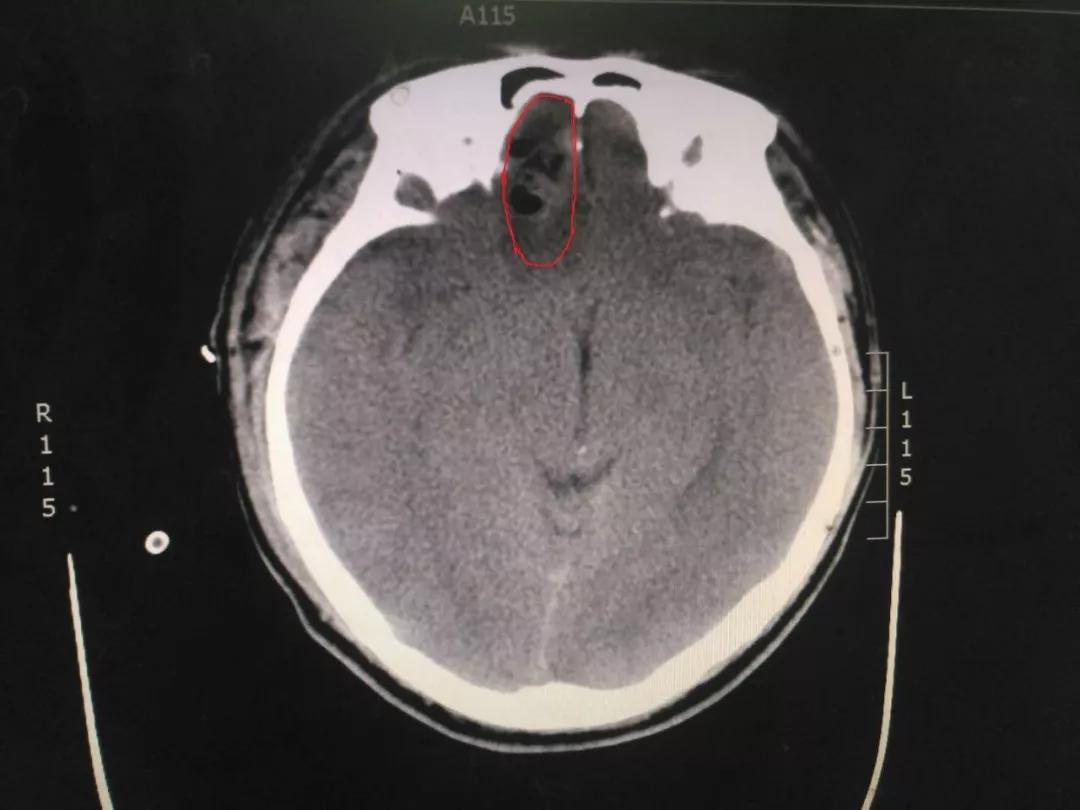

初步诊察发现患者右侧瞳孔散大,CT结果显示右侧额叶脑挫裂伤,部分血肿位于前颅凹底,位置深,清除困难,这给治疗带来了一定的难度。王占尧主任医师随即决定应用神经内镜辅助清除血肿,并采用右侧额颞弧形切口,避免采取传统的双额冠状切口,骨窗大小仅有4cmX4cm,大大减少了手术创伤,也相应减少了住院手术的费用,减轻了患者负担。术后第二天,患者意识恢复,复查CT显示血肿清除效果满意。